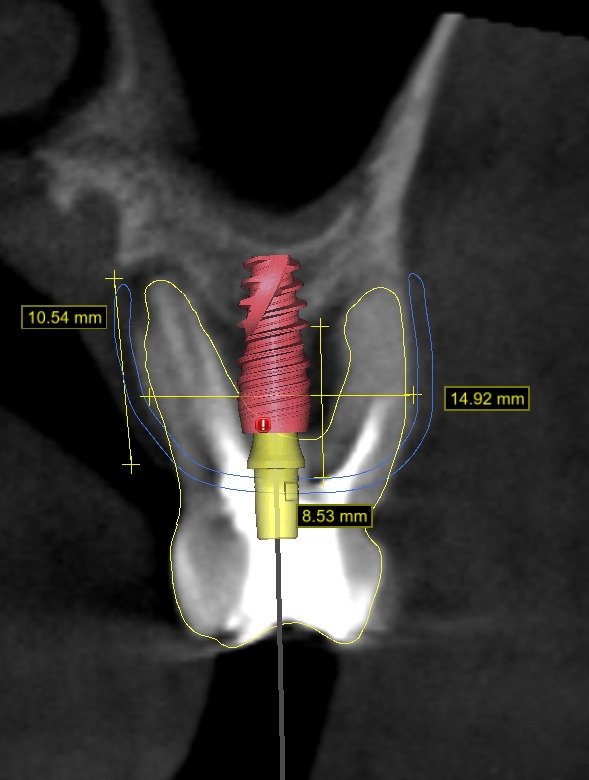

• Diagnóstico tomográfico (CBCT): lectura enfocada en regeneración ósea.

• Análisis del defecto óseo: tipo, morfología y severidad.

• Planificación del caso desde el resultado protésico.

• Planificación de tornillos de fijación:

• Número

• Posición

• Angulación